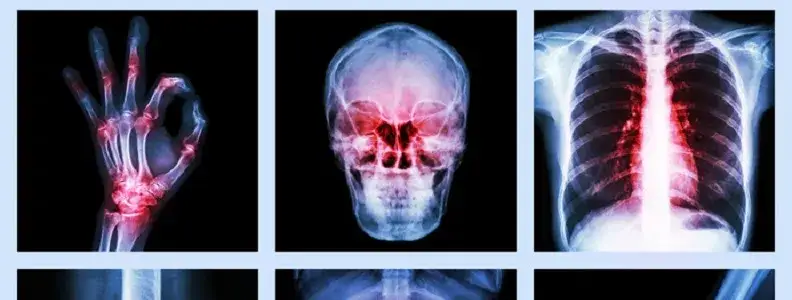

Niedobór witaminy K2 objawia się problemami z krzepnięciem, osłabieniem kości i zwapnieniem tętnic

- Wczesne objawy niedoboru obejmują zwiększoną skłonność do siniaków, krwawienia z nosa i dziąseł oraz dłuższe gojenie się ran.

- Długoterminowy deficyt prowadzi do osteoporozy, zwiększonego ryzyka złamań i zwapnienia tętnic, co zagraża sercu.

Z mojego doświadczenia wynika, że zrozumienie mechanizmów działania witaminy K2 jest fundamentalne dla docenienia jej znaczenia. Witamina K2 działa jak swoisty "dyrygent" dla wapnia w naszym ciele. Aktywuje ona dwa kluczowe białka: osteokalcynę, która transportuje wapń do kości i zębów, oraz białko MGP (Matrix Gla Protein), które zapobiega odkładaniu się wapnia w miejscach, gdzie jest on niepożądany czyli w naczyniach krwionośnych, chrząstkach i innych tkankach miękkich. Bez odpowiedniej ilości K2, wapń może gromadzić się w tętnicach, prowadząc do ich zwapnienia i usztywnienia. Oprócz tej kluczowej funkcji, witamina K2, podobnie jak K1, bierze udział w procesie krzepnięcia krwi, choć jest to jej mniej dominująca rola.

To jest chyba najbardziej podstępny i niebezpieczny skutek niedoboru witaminy K2. Mówię tu o kalcyfikacji, czyli zwapnieniu tętnic. Bez aktywnego białka MGP, które wiąże wapń w naczyniach krwionośnych i zapobiega jego odkładaniu, wapń zaczyna gromadzić się w ścianach tętnic. Powoduje to, że naczynia stają się sztywne, tracą elastyczność i są bardziej podatne na uszkodzenia. Ten proces jest kluczowym czynnikiem rozwoju miażdżycy, choroby wieńcowej, a także nadciśnienia. Zwapnienie tętnic to cichy zabójca, który przez lata nie daje żadnych objawów, a kiedy już się pojawią, często jest za późno. Dlatego profilaktyka poprzez odpowiednią podaż K2 jest tak ważna dla zdrowia serca i całego układu krążenia.